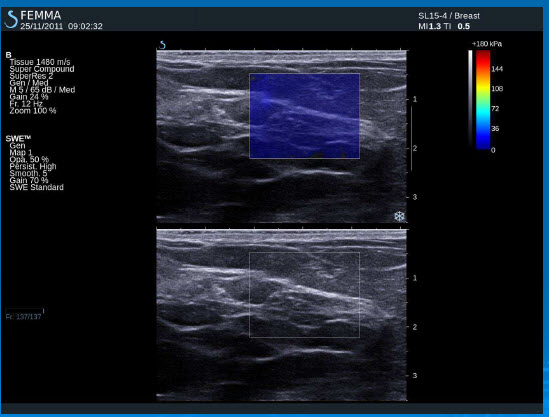

- výstupem elastografie je ultrazvukový B-obraz překrytý barevnou mapou. Každému bodu tkáně je přiřazena barva, která kóduje jeho elastické vlastnosti.

Barevné mapy v elastografickém obraze Modrá barva – měkká solidní tkáň (normální fibroglandulární tkáň), viskózní tekutina v cystách

Barevná škála – tuhá tkáň (maligní)

Černé výpadky – čistá tekutina (cysty) – příčné vlny se nešíří

– tuhá tkáň – příčné vlny jsou velmi slabé – jsou tlumeny, rychlá propagace příčných vln do okolí

Normální tkáň prsu